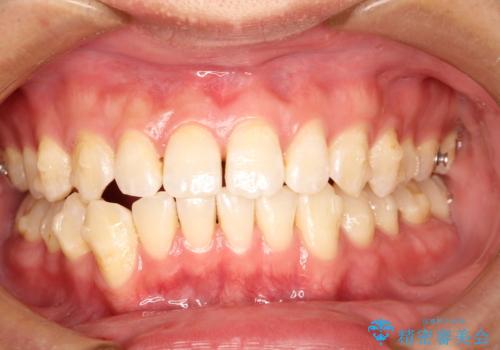

前歯がガタガタ インビザラインによる矯正

- 前歯がガタガタ、下の犬歯が飛び出ているのを主訴に来院されました。

下の奥歯を後方へ移動させてスペースを確保して、前歯を並べる計画としました。

目立たない装置をご希望されたので、インビザラインにて矯正治療を行いました。